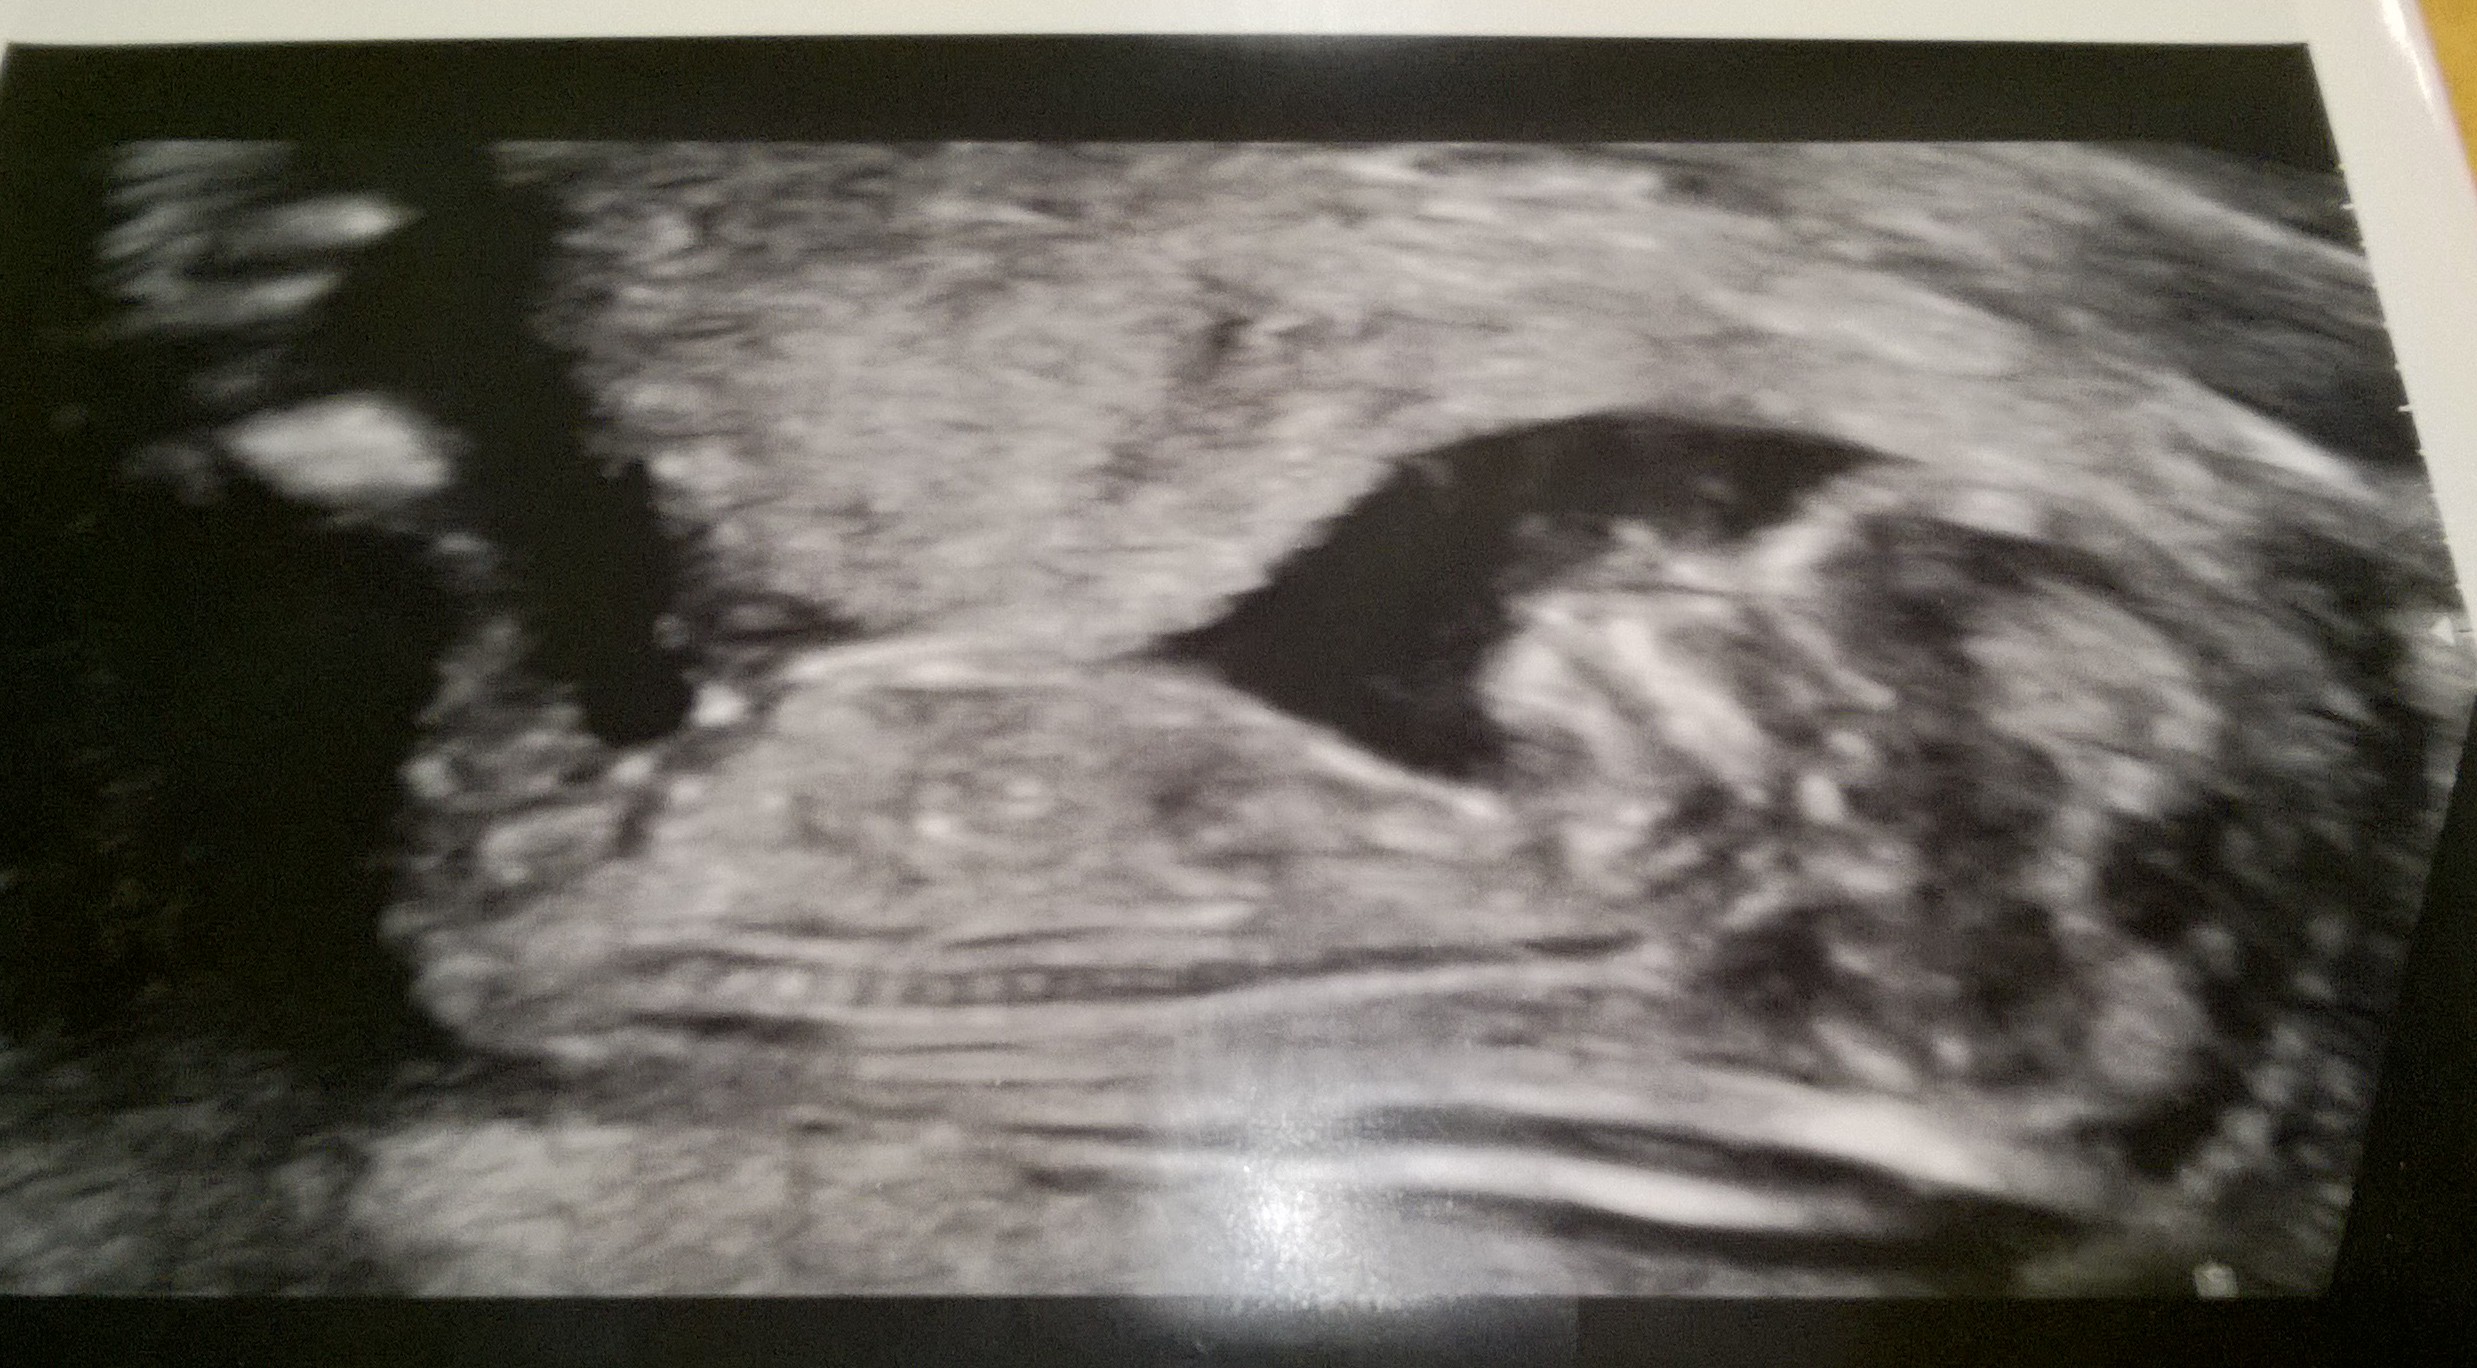

Niin ja tässä vielä kuva kun aiemmin unohtui:

WP_20160212_004.jpg

Rv 12+1 (ultra 12+5)

Ja sori, tän jälkeen lakkaan spoilaamasta tätä palstaa näillä kuvilla. Tiiän et ei ehkä oo tän ketjun juttu mut jospa tää lois jotain toivonkipinää jollekulle! <3

Maggie miten söpö vauva tulos ♡ mä uskon sulla siihen 12+5 sitte, kaverilla nimittäin meni niin että ensi la 3.11, sitte muutettiin ar-ultran perusteella yli viikolla, nt-ultras johki 8.11, loppuviimeen se kasvoki koko ajan se 3.11 mukaan. :) se on jännä miten toisis paikois vaihdetaan parin päivän heitonki takia ja toisis ei alle 5pv heitoilla.

Maggie, voi mikä ihana siellä polskii :)

Maggie, hieno kuva! :)

Maggie voi ihana <3